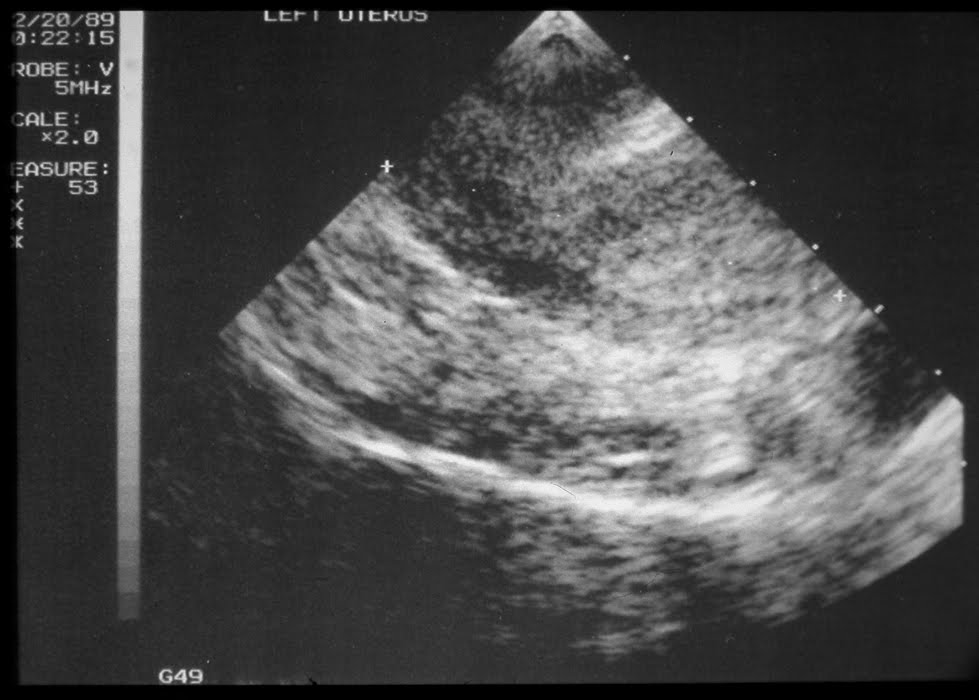

Patient #2 (bicornuate uterus). View left of the midline. Normal uterus with endometrial stripe seen. Top of uterus on the right of the screen.

Sagittal (midline) view. No uterus seen. This is a bicornuate uterus.